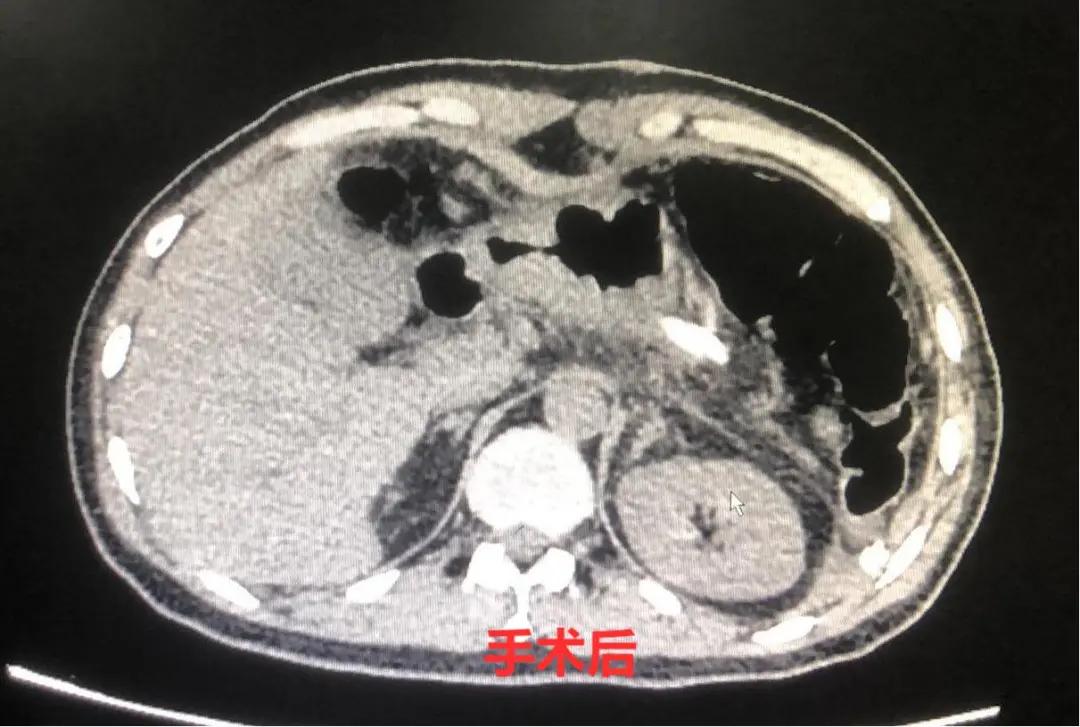

3月3日上午10点,手术正式开始。逐层打开腹腔后,项红军主任发现张先生的腹腔比预想的“干净”,几乎看不到转移的淋巴结,周围的组织粘连也没那么严重,整个肿瘤分离都比较顺利。

手术历时2小时,非常成功,不仅切除了胰腺的原发病灶,就连射频消融后肝内坏死组织也一并清除干净,彻底解除了张先生的后顾之忧。